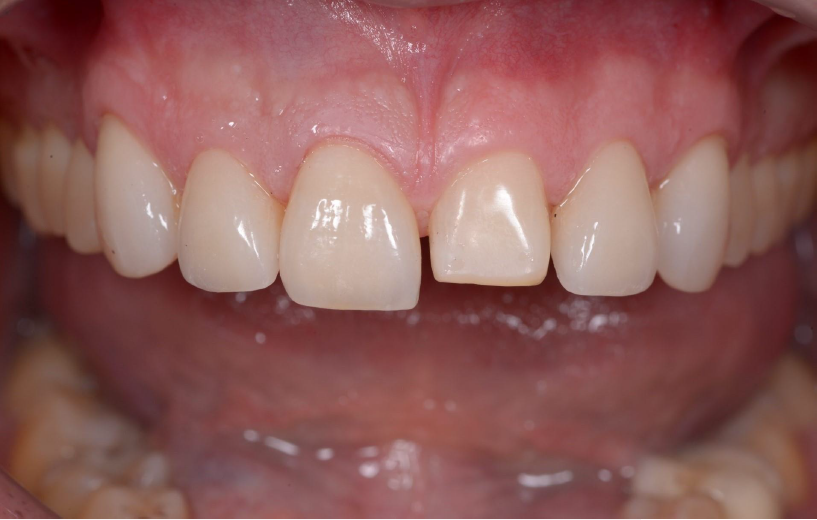

Close-up of teeth with the mouth slighty open

3M™ Protemp™ 4 Temporization Material mock-up placed with a wax-up impression.